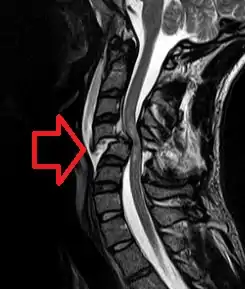

![]() | |

| MRI of a fractured and dislocated cervical vertebra (C4) in the neck that is compressing the spinal cord | |

Diagnosis

A person's presentation in context of trauma or non-traumatic background determines suspicion for a spinal cord injury. The features are namely paralysis, sensory loss, or both at any level. Other symptoms may include incontinence.[89]

A radiographic evaluation using an X-ray, CT scan, or MRI can determine if there is damage to the spinal column and where it is located.[9] X-rays are commonly available[88] and can detect instability or misalignment of the spinal column, but do not give very detailed images and can miss injuries to the spinal cord or displacement of ligaments or disks that do not have accompanying spinal column damage.[9] Thus when X-ray findings are normal but SCI is still suspected due to pain or SCI symptoms, CT or MRI scans are used.[88] CT gives greater detail than X-rays, but exposes the patient to more radiation,[90] and it still does not give images of the spinal cord or ligaments; MRI shows body structures in the greatest detail.[9] Thus it is the standard for anyone who has neurological deficits found in SCI or is thought to have an unstable spinal column injury.[91]